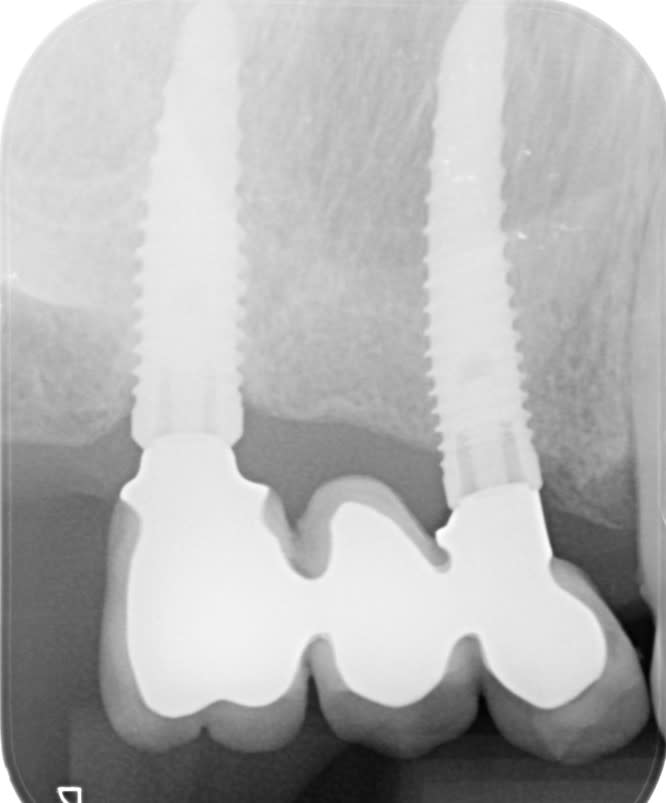

Selon la patiente qui, comme d'hab a pas eu ou a perdu son passeport..

46 Konebel replace.... je dirais nobel mais...

24 Nobel.

Implants posés en 2013 2014...

Les radios sont pas top... je la revois vendredi 9...

Oui c’est du replace tapered, trilobe, pas les CC….

Question: l'implant 13 a l'air différent de la 15 au niveau du col...

Mon protho me dit qu'il existe 3 modéles, wide, narrow et regular.... une idée de ce à quoi j'ai affaire?

tu as 2 tailles différentes c'est certain....mais c'est toi avec ton logiciel d'imagerie qui peut faire la distinction....je dirais soit un narrow (étroit) et un regular, soit un regular et un wide (large)